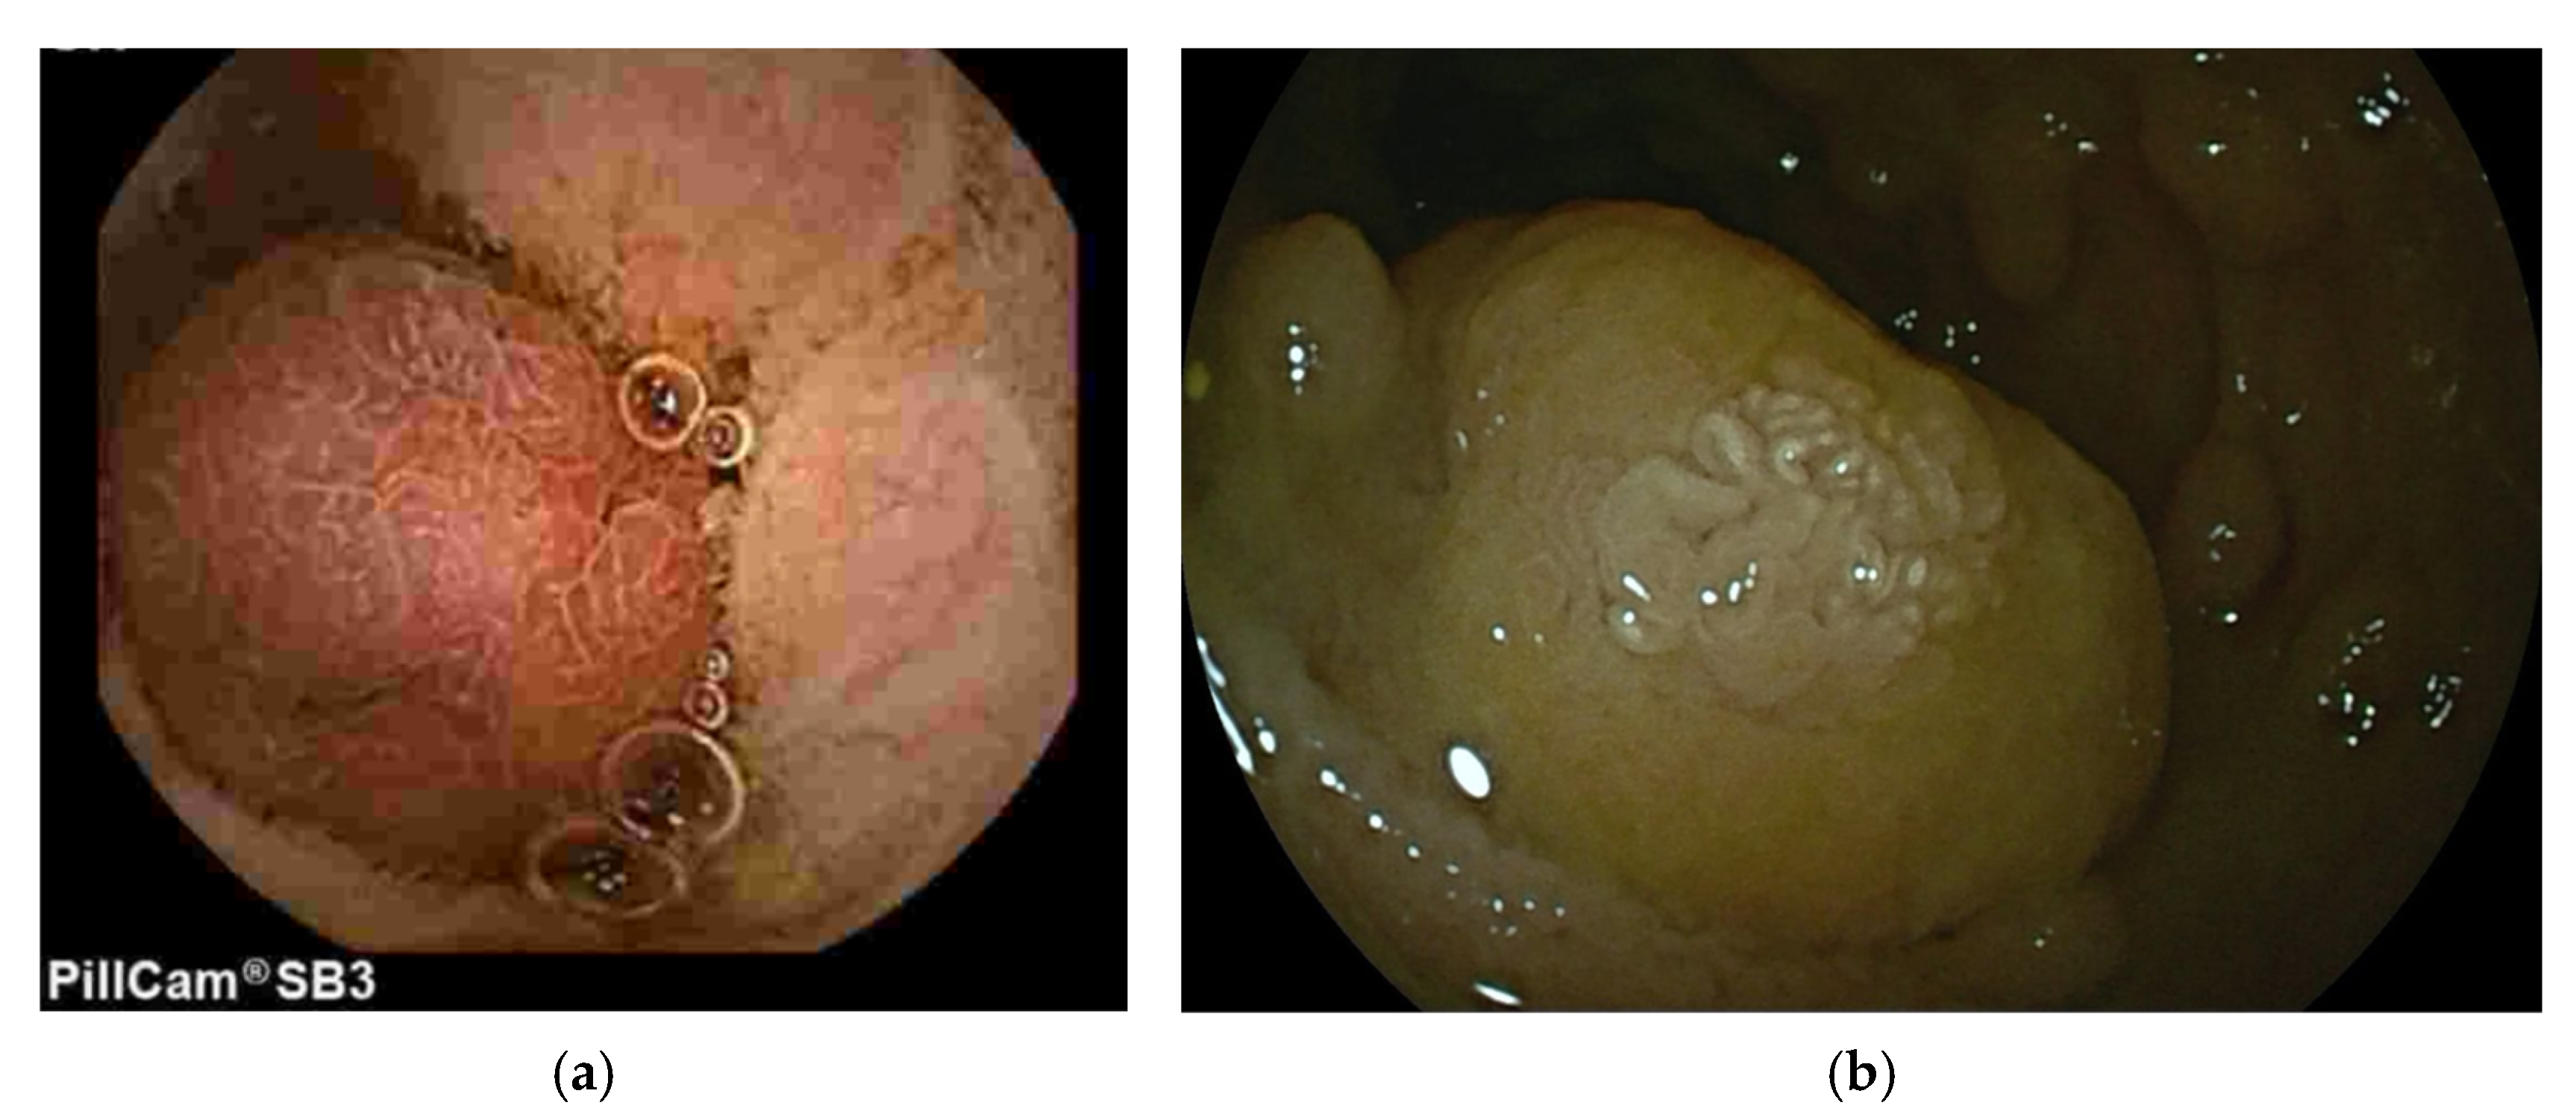

3.3. Juvenile Polyposis Syndrome (JPS)